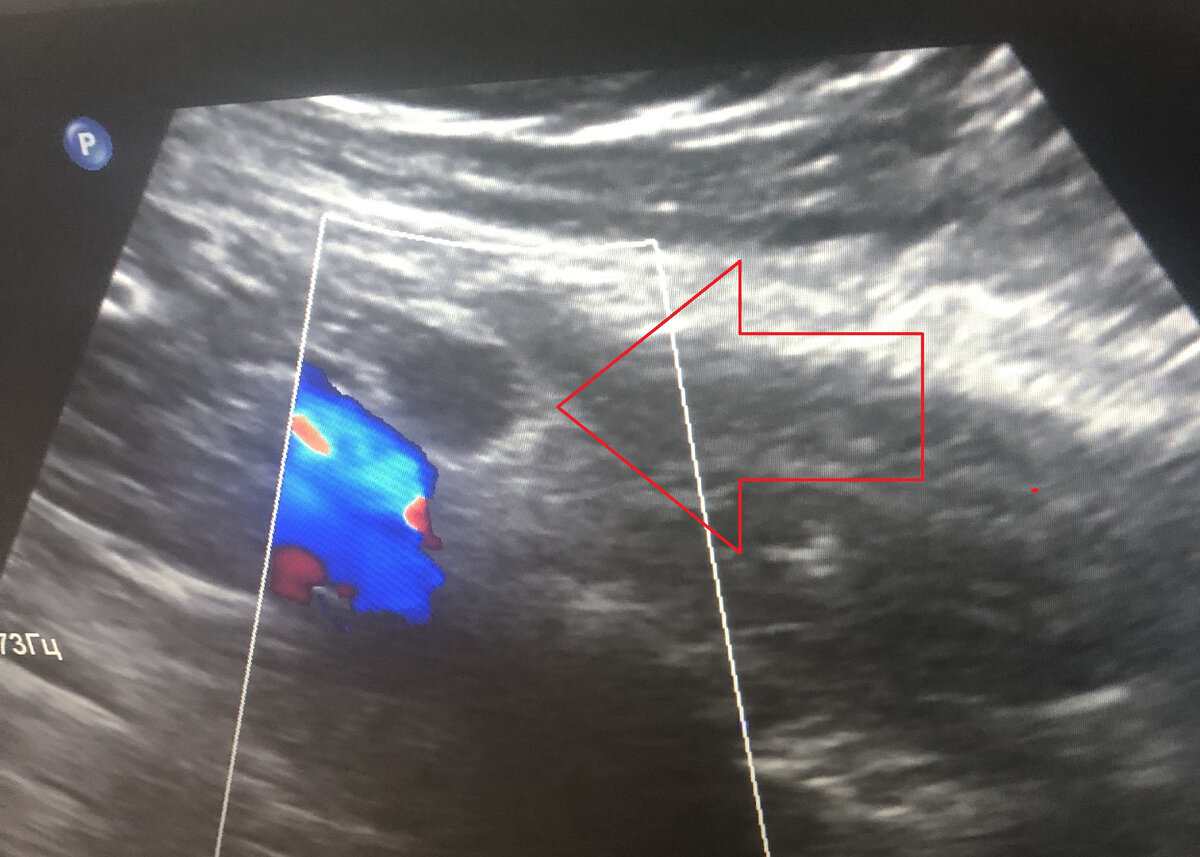

И только через 4 года после последнего прогрессирования и, соответственно, через 8 лет после первой операции по данным ПЭТ-КТ снова подозрение на прогрессирование - в наружном подвздошном лимфоузле справа подозрительная гиперфиксация радиоактивной глюкозы (SUVmax 8,83), форма лимфоузла при этом округлая, плотность повышена, а размер до 1,5 см.

Узел был расположен чуть выше крупных наружных подвздошных сосудов